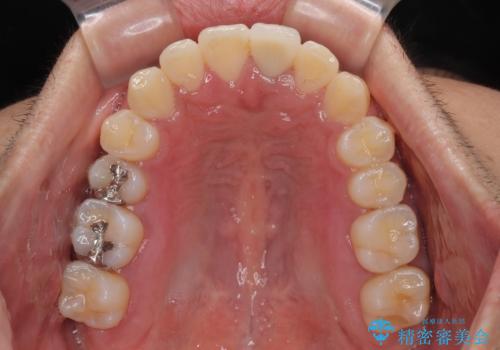

矯正治療後には気になっていた前歯をセラミッククラウンにし、自然な口元に仕上げることができました。